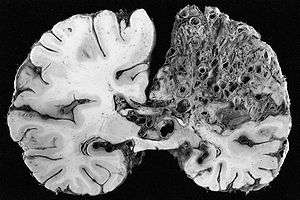

This coronal cross-section of a brain reveals a significant arteriovenous malformation that occupies much of the parietal lobe.

Neuropathology is the study of disease of nervous system tissue, usually in the form of either surgical biopsies or sometimes whole brains in the case of autopsy. Neuropathology is a subspecialty of anatomic pathology, neurology, and neurosurgery. In many English-speaking countries, neuropathology is considered a subfield of anatomical pathology. A physician who specializes in neuropathology, usually by completing a fellowship after a residency in anatomical or general pathology, is called a neuropathologist. In day-to-day clinical practice, a neuropathologist is a consultant for other physicians. If a disease of the nervous system is suspected, and the diagnosis cannot be made by less invasive methods, a biopsy of nervous tissue is taken from the brain or spinal cord to aid in diagnosis. Biopsy is usually requested after a mass is detected by medical imaging. With autopsies, the principal work of the neuropathologist is to help in the post-mortem diagnosis of various conditions that affect the central nervous system. Biopsies can also consist of the skin. Epidermal nerve fiber density testing (ENFD) is a more recently developed neuropathology test in which a punch skin biopsy is taken to identify small fiber neuropathies by analyzing the nerve fibers of the skin. This test is becoming available in select labs as well as many universities; it replaces the traditional nerve biopsy test as less invasive.